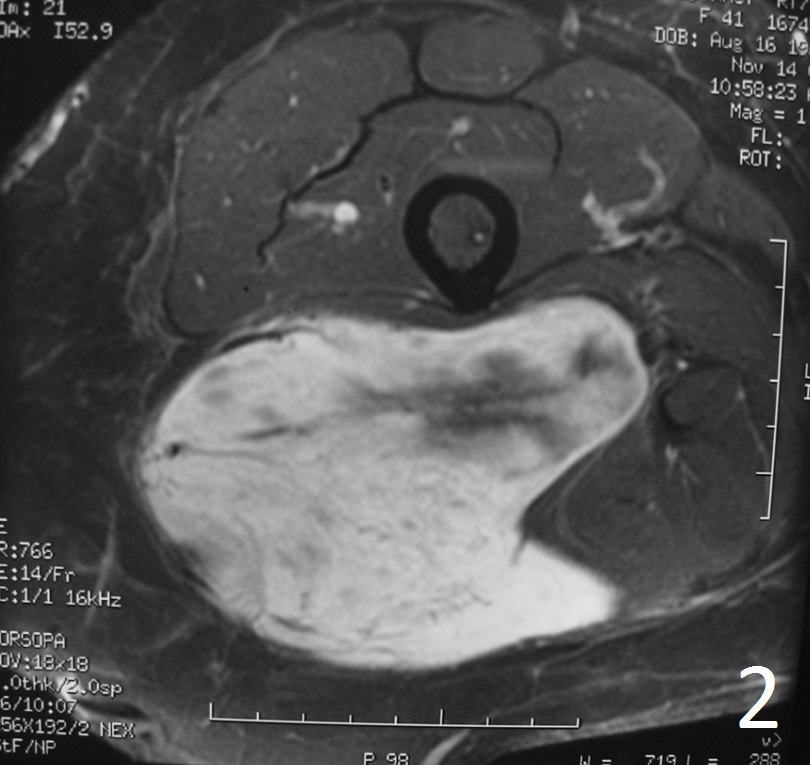

Fig. 1-2: The MRI of a solitary fibrous tumor is non specific. Any type of sarcoma can appear similar. Axial MRI of the thigh shows a well circumscribed and big lobulated mass low/intermediate signal on T1W (Fig. 1), enhancement on T1W FS post-gadolinium images with some areas of necrosis (Fig. 2).